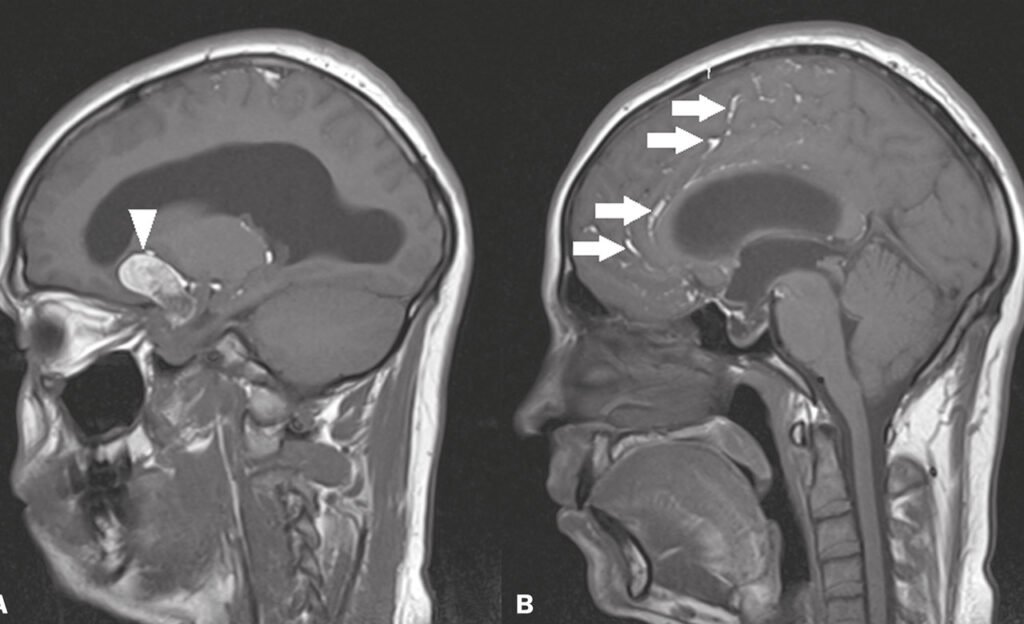

Cistos Cerebrais

➤ O que são? Cistos cerebrais são cavidades preenchidas por líquido que se formam dentro ou ao redor do cérebro. Ao contrário dos tumores, eles não […]